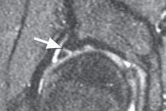

Labral repair is best suited for young patients when it is believed that simple débridement may result in inordinate sacrifice of healthy tissue ( TECH FIG 2).

1.

An optimal pattern is a tear at the articulolabral junction where a large segment of otherwise healthy tissue has been detached.

2.

Labral function is most dependent on its fluid seal.2 Thus, the goal of repair is to reapproximate the labrum to the adjacent acetabulum.

3.

The mechanical properties of the labrum are minimal; therefore, the recreation of a bolster effect such as that in the shoulder is not necessary.

---

A D E TECH FIG 2 • A. Sagittal MRA image demonstrates an anterior labral tear (

arrow

). B. Arthroscopy reveals a traumatic detachment of the anterior labrum (indicated by the probe). C. An anchor has been placed with suture limbs passed in a mattress fashion through the detached labrum. D. The labrum has been reapproximated to the articular edge. E. Viewing the peripheral aspect of the labrum, the suture is seen on its capsular surface, avoiding contact with the articular surface of the femoral head. (Courtesy of J. W. Thomas Byrd, MD.) ### TECHNIQUES